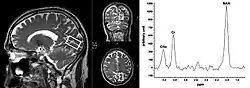

Als Magnetresonanzspektroskopie (MRS) wird in der Medizin und Biochemie ein auf der Kernspinresonanz basierendes Verfahren bezeichnet, mit dem biochemische Beobachtungen ortsaufgelöst in einem Volumenelement durchgeführt werden können. Damit können verschiedene chemische Substanzen (siehe Metaboliten) im lebenden Gewebe aufgrund ihrer chemischen Verschiebung identifiziert und quantifiziert werden.[1]

Mit Hilfe der 1H-MRS an einer klinischen Magnetresonanztomografie-Anlage können N-Acetylaspartat als neuronaler Marker oder Cholin-enthaltende Moleküle als Zellmembran-Marker nachgewiesen werden. Außerdem sind Laktat und Citrat sowie die CH2- und CH3-Gruppen von Lipiden und anderen Makromolekülen detektierbar. Die 31P-MRS dient hauptsächlich zur Untersuchung des zellulären Energiestoffwechsels, während die 13C-MRS einen Einblick in den zellulären Glucose-Stoffwechsel gewährt.[4] Klinische Studien sind hauptsächlich an Gehirn, Skelettmuskel, Herz, Leber und Prostata durchgeführt worden.[4][5] In den letzten Jahren haben klinische MRS-Studien in der Onkologie deutlich zugenommen.[6]

Bei der MRS kann ein bestimmtes Volumen, das vorher auf Übersichtsbildern positioniert wird, in einem Gewebe gemessen werden. Diese Methode wird auch als Single-Voxel-Spektroskopie (SVS) bezeichnet.[9] Es ist auch möglich, mehrere Voxel gleichzeitig zu messen, wobei ein größeres lokalisiertes Volumen durch Phasenkodierung in mehrere kleine Volumina unterteilt wird. Diese Methode nennt sich Multivoxel-Spektroskopie oder Chemical Shift Imaging (CSI) und kann in zwei oder drei Dimensionen ausgeführt werden.[10]